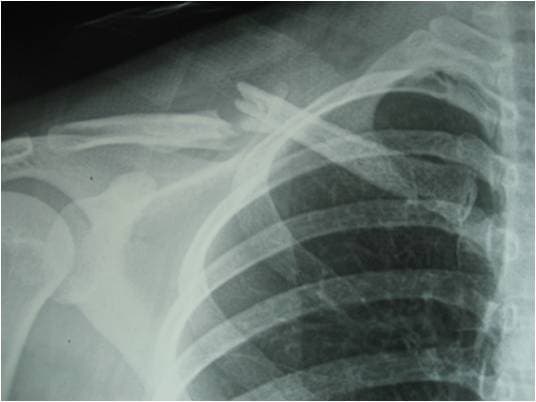

Gãy xương đòn là chấn thương hay gặp nhất khi bị ngã đập vai xuống đất. Phẫu thuật gãy xương đòn là một trong những phương pháp điều trị chính trong các trường hợp nghiêm trọng, ảnh hưởng tới sinh hoạt hàng ngày. Là địa chỉ uy tín thực hiện thành công nhiều ca phẫu thuật gãy xương đòn, Bệnh viện Đa khoa Quốc tế Thu Cúc cũng là nơi chăm sóc y tế rất hiệu quả. Tại đây, người bệnh được hồi phục nhanh chóng với chất lượng dich vụ chuyên nghiệp và chi phí hợp lý.

Xương đòn còn được gọi là xương quai xanh, là một trong những xương quan trọng của thành ngực trước. Xương đòn có hình dạng dẹt, cong theo hình chữ S. Một đầu xương tiếp khớp với xương ức, đầu còn lại tiếp khớp với xương bả vai. Chấn thương gãy xương đòn nếu chỉ bị nhẹ, các bác sĩ thường điều trị bằng phương pháp bảo tồn. Tuy nhiên có nhiều trường hợp người bệnh gãy xương đòn được chỉ định phẫu thuật. Phẫu thuật gãy xương đòn được đánh giá là an toàn, đơn giản do vị trí của xương đòn nằm nông dưới da. Phẫu thuật này được chỉ định khá thường xuyên.